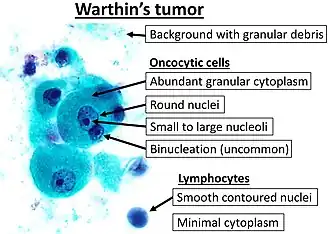

| Cytopathology of Warthin's tumor, with typical cellular features (and a relatively uncommon binucleated cell).[1] Pap stain. | |

The appearance of this tumor under the microscope is unique. There are cystic spaces surrounded by two uniform rows of oncocytes, which are epithelial cells with abundant, granular, eosinophilic cytoplasm.[7] The cystic spaces have epithelium referred to as papillary infoldings that protrude into them. Additionally, the epithelium has lymphoid stroma with germinal center formation.

- ^ Image by Mikael Häggström, MD. References for entries:

- Köybaşioğlu FF, Önal B, Han Ü, Adabağ A, Şahpaz A (2020). "Cytomorphological findings in diagnosis of Warthin tumor". Turk J Med Sci. 50 (1): 148–154. doi:10.3906/sag-1901-215. PMC 7080357. PMID 31769640.{{cite journal}}: CS1 maint: multiple names: authors list (link)

Binucleation:

- Dr.S. Malliga (2006-10-18). "A correlative cytological and histopathological study on lesions of salivary gland" (PDF).

- Chan MKM, McGuire LJ: Cytodiagnosis of Lesions Presenting as Salivary Gland Swellings: A Report of Seven Cases. Diagn Cytopathol 8: 439-443, 1992b. - ^ Witt RL, ed. (2005). "Chapter 9 "Benign tumors, cysts, and tumor-like conditions of the salivary glands". Salivary Gland Diseases: Surgical and Medical Management. New York: Thieme Medical Publishers. p. 123. ISBN 1-58890-414-8.